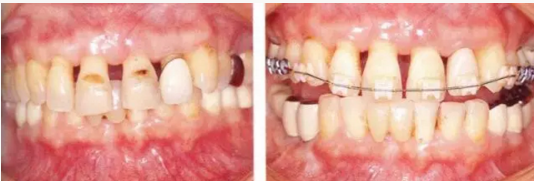

111.png

▲圖16-5,6

1111.png

▲圖16-7

▲圖16-5~7 將左上1和右上1拔除,下頜磨牙區(qū)植入種植體,全口進(jìn)行牙周外科處理后,佩戴臨時(shí)修復(fù)體。圖16-7為佩戴臨時(shí)修復(fù)體后的狀態(tài)。由于左上2,3和右上2,3仍然前突,所以覆蓋較深。

111111.png

▲圖16-8~10

切斷左上2,3和右上2,3的連接部,使用活動(dòng)矯治器進(jìn)行正畸治療。

0.png

▲圖16-11,12

▲圖16-11 正畸治療結(jié)束后的研究模型。覆蓋有所改善。

▲圖16-12 佩戴最終修復(fù)體后的狀態(tài)。